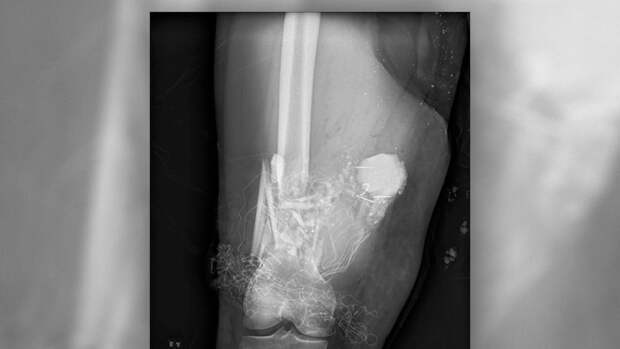

Спортсмен получил тяжелые травмы во время приседа со штангой весом в 250 килограммов. Пауэрлифтер был доставлен в больницу с переломом голени, а также с закрытым перелом двух берцовых костей на ноге.